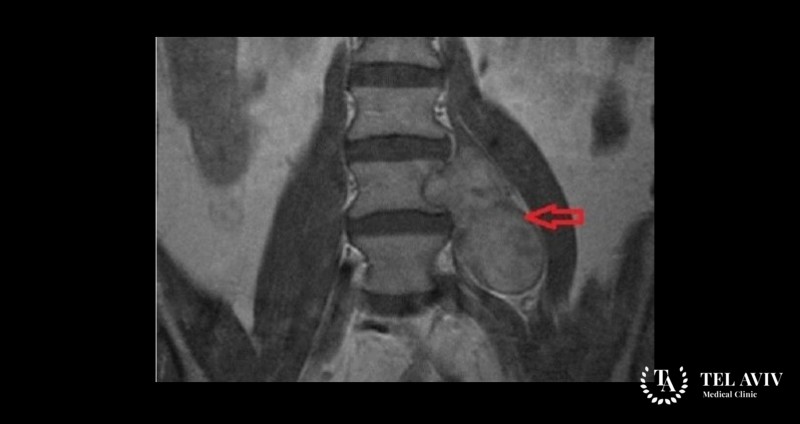

На первых этапах роста обнаружить заболевание проблематично из-за отсутствия симптомов. Нередко выявляется опухоль случайно при рентгенографии позвоночника, проводимой по совсем другим причинам. При подозрении на новообразование в израильской клинике Tel Aviv Medical Clinic проводится детальная диагностика, чтобы дифференцировать заболевание. Такие современные методики обследования как: КТ, МРТ, сцинтиграфия, миелография, позволяют выявить наличие повреждения позвоночника, изменение его структур, определить характер, форму и стадию развития опухоли.